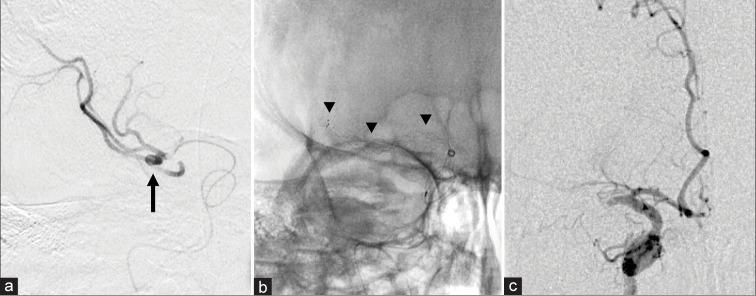

CASE DESCRIPTION

A 46-year-old patient with the right internal carotid artery terminal occlusion presented with the left-sided hemiparesis, hemispatial neglect, and dysarthria and underwent MT. Initial thrombectomy using a stent retriever and reperfusion catheter was unsuccessful. Angiography just before the second attempt showed SAH. Fortunately, we achieved recanalization of the thrombolysis in cerebral infarction 2b and hemostasis by lowering the blood pressure followed by coil embolization of the ruptured aneurysm. Only a few cases of ruptured aneurysms have been reported during MT using a stent retriever. Stent withdrawal is suspected to cause aneurysm rupture in cases with an unknown hidden middle cerebral artery bifurcation aneurysm.

1例右侧颈内动脉末端闭塞的46岁患者,表现为左侧偏瘫、偏侧空间忽视和构音障碍,接受了MT。首次使用支架取栓器和再灌注导管进行取栓未成功。第二次尝试前的血管造影显示SAH。幸运的是,我们实现了脑梗死2b级溶栓再通,并通过降低血压实现止血,随后对破裂动脉瘤进行弹簧圈栓塞。使用支架取栓器进行MT期间发生动脉瘤破裂的病例仅有少数报道。对于隐匿性大脑中动脉分叉动脉瘤病例,怀疑支架回撤会导致动脉瘤破裂。